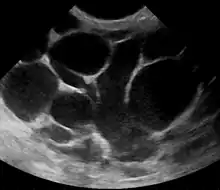

The diagnosis of mastitis and breast abscess can usually be made based on a physical examination.[24] The doctor will also take into account the signs and symptoms of the condition.

However, if the doctor is not sure whether the mass is an abscess or a tumor, a breast ultrasound may be performed. The ultrasound provides a clear image of the breast tissue and may be helpful in distinguishing between simple mastitis and abscess or in diagnosing an abscess deep in the breast. The test consists of placing an ultrasound probe over the breast.